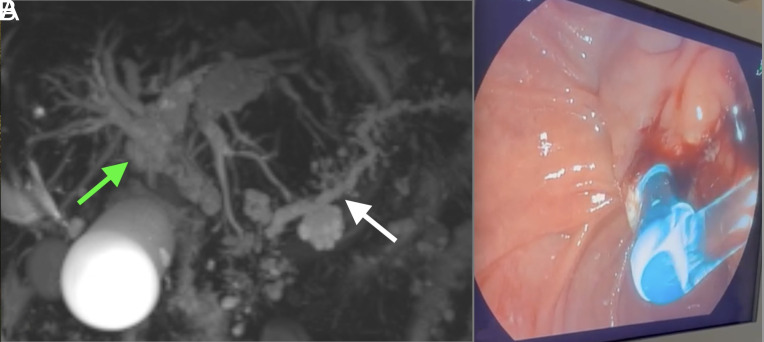

White Bile Detected During Endoscopic Retrograde Cholangiopancreatography: A Rare Phenomenon and Its Clinical Implications.